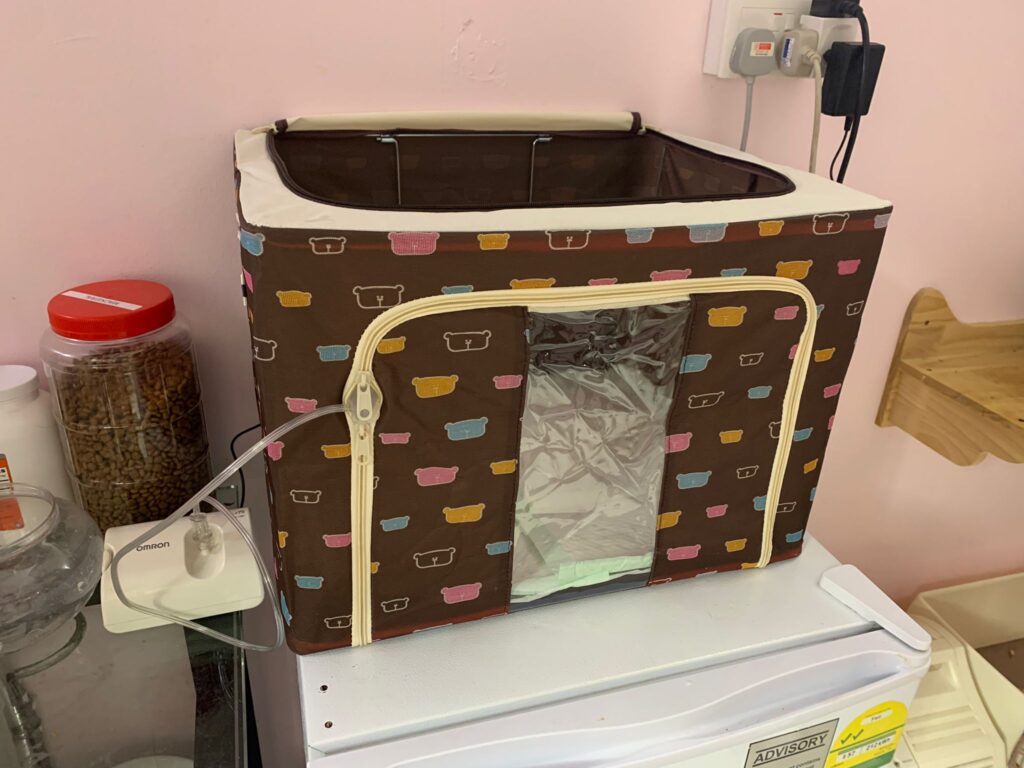

Morning: he is fine, didn’t hear him cough or sneeze. He is eating well. today I started nubulizing him, set up a bear box in 5G for his nubulizing. he did meow but not any extreme reaction in there. Wow smoky when I open up to let him out. think can do that for Jack or so when I’m in longer hours.

Didi 4.9.22 Thurs

Day: today nubulize him again day 02 – Quite steady already. 🙂